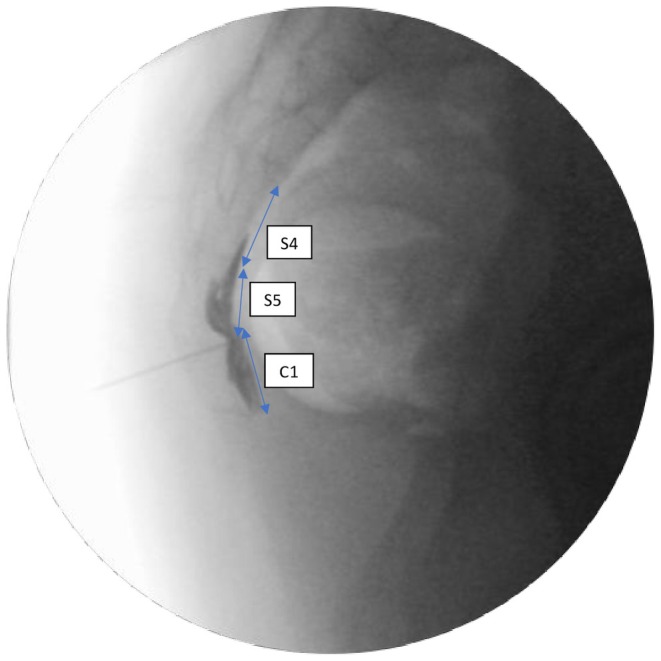

Abstract Image